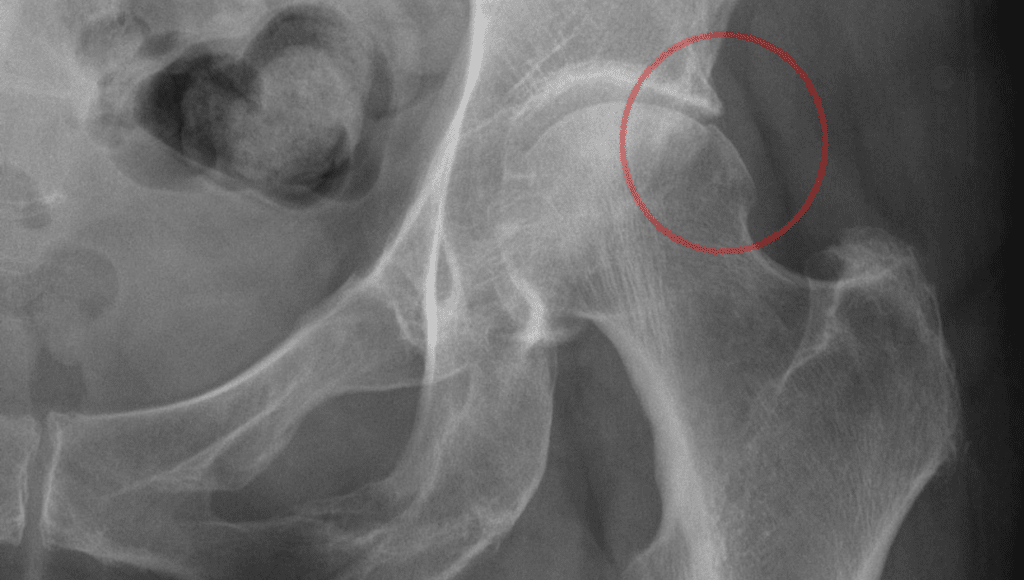

- Cam: In cam, impingement of the femoral head causes the joint to be unable to rotate smoothly. A bump forms on the border of the femoral head which grinds the cartilage inside the acetabulum.

- X-rays: These will show whether the hip has shaped bones of FAI, and provide images of the bone. X-rays may also reveal signs of arthritis.